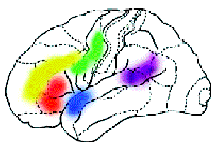

Найдены микроучастки мозга, которые отвечают за счёт, за различение конкретных и абстрактных слов. Показаны различия в работе нейронов при восприятии слова родного языка (чашка), квазислова родного языка (чохна) и слова иностранного (вахт — время по-азербайджански). В этой деятельности по-разному участвуют нейроны коры и глубоких структур мозга. В глубоких структурах в основном наблюдается увеличение частоты электрических разрядов, не очень „привязанное“ к какой-то определённой зоне. Эти нейроны как бы любую задачу решают всем миром. Совершенно другая картина в коре головного мозга. Один нейрон словно говорит: „А ну-ка, ребята, помолчите, это моё дело, и я буду выполнять его сам“. И действительно, у всех нейронов, кроме некоторых, понижается частота импульсации, а у „избранников“ повышается. Благодаря технике позитронно-эмиссионной томографии (или сокращённо ПЭТ) стало возможно детальное изучение одновременно всех областей мозга, отвечающих за сложные „человеческие“ функции. Суть метода состоит в том, что малое количество изотопа вводят в вещество, участвующее в химических превращениях внутри клеток мозга, а затем наблюдают, как меняется распределение этого вещества в интересующей нас области мозга. Если к этой области усиливается приток глюкозы с радиоактивной меткой — значит, увеличился обмен веществ, что говорит об усиленной работе нервных клеток на этом участке мозга. А теперь представьте, что человек выполняет какое-то сложное задание, требующее от него знания правил орфографии или логического мышления. При этом у него наиболее активно работают нервные клетки в области мозга, „ответственной“ именно за эти навыки. Усиление работы нервных клеток можно зарегистрировать с помощью ПЭТ по увеличению кровотока в активизированной зоне. Таким образом удалось определить, какие области мозга „отвечают“ за синтаксис, орфографию, смысл речи и за решение других задач. Например, известны зоны, которые активизируются при предъявлении слов, неважно, надо их читать или нет. Есть и зоны, которые активизируются, чтобы „ничего не делать“, когда, например, человек слушает рассказ, но не слышит его, следя за чем-то другим. Что такое внимание? Не менее важно понять, как „работает“ внимание у человека. Этой проблемой в нашем институте занимается и моя лаборатория, и лаборатория Ю.Д. Кропотова. Исследования ведутся совместно с коллективом учёных под руководством финского профессора Р. Наатанена, который открыл так называемый механизм непроизвольного внимания. Чтобы понять, о чём идёт речь, представьте ситуацию: охотник крадётся по лесу, выслеживая добычу. Но он и сам является добычей для хищного зверя, которого не замечает, потому что настроен только на поиск оленя или зайца. И вдруг случайный треск в кустах, может быть, и не очень заметный на фоне птичьего щебета и шума ручья, мгновенно переключает его внимание, подаёт сигнал: „Рядом опасность“. Механизм непроизвольного внимания сформировался у человека в глубокой древности, как охранный механизм, но работает и сейчас: например, водитель ведёт машину, слушает радио, слышит крики детей, играющих на улице, воспринимает все звуки окружающего мира, внимание его рассеянно, и вдруг тихий стук мотора мгновенно переключает его внимание на машину — он осознаёт, что с двигателем что-то не в порядке (кстати, это явление похоже на детектор ошибок). Такой переключатель внимания работает у каждого человека. Мы обнаружили зоны, которые активизируются на ПЭТ при работе этого механизма, а Ю.Д. Кропотов исследовал его с помощью метода имплантированных электродов. Иногда в самой сложной научной работе бывают смешные эпизоды. Так было, когда мы в спешке закончили эту работу перед очень важным и престижным симпозиумом. Ю.Д. Кропотов и я поехали на симпозиум делать доклады, и только там с удивлением и „чувством глубокого удовлетворения“ неожиданно выяснили, что активизация нейронов происходит в одних и тех же зонах. Да, иногда двоим сидящим рядом надо поехать в другую страну, чтобы поговорить.

Если механизмы непроизвольного внимания нарушаются, то можно говорить о болезни. В лаборатории Кропотова изучают детей с так называемым дефицитом внимания и гиперактивностью. Это трудные дети, чаще мальчики, которые не могут сосредоточиться на уроке, их часто ругают дома и в школе, а на самом деле их нужно лечить, потому что у них нарушены некоторые определённые механизмы работы мозга. Ещё недавно это явление не рассматривалось как болезнь и лучшим методом борьбы с ним считались „силовые“ методы. Мы сейчас можем не только определить это заболевание, но и предложить методы лечения детей с дефицитом внимания. Однако хочется огорчить некоторых молодых читателей. Далеко не каждая шалость связана с этим заболеванием, и тогда… „силовые“ методы оправданы. Кроме непроизвольного внимания есть ещё и селективное. Это так называемое „внимание на приёме“, когда все вокруг говорят разом, а вы следите только за собеседником, не обращая внимания на неинтересную вам болтовню соседа справа. Во время эксперимента испытуемому рассказывают истории: в одно ухо — одну, в другое — другую. Мы следим за реакцией на историю то в правом ухе, то в левом и видим на экране, как радикально меняется активизация областей мозга. При этом активизация нервных клеток на историю в правом ухе значительно меньше — потому, что большинство людей берут телефонную трубку в правую руку и прикладывают её к правому уху. Им следить за историей в правом ухе проще, нужно меньше напрягаться, мозг возбуждается меньше. Тайны мозга ещё ждут своего часа Мы часто забываем очевидное: человек — это не только мозг, но ещё и тело. Нельзя понять работу мозга, не рассматривая всё богатство взаимодействия мозговых систем с различными системами организма. Иногда это очевидно — например, выброс в кровь адреналина заставляет мозг перейти на новый режим работы. В здоровом теле — здоровый дух — это именно о взаимодействии тела и мозга. Однако далеко не всё здесь понятно. Изучение этого взаимодействия ещё ждёт своих исследователей. Сегодня можно сказать, что мы хорошо представляем, как работает одна нервная клетка. Многие белые пятна исчезли и на карте мозга, определены области, отвечающие за психические функции. Но между клеткой и областью мозга находится ещё один, очень важный уровень — совокупность нервных клеток, ансамбль нейронов. Здесь пока ещё много неясного. С помощью ПЭТ мы можем проследить, какие области мозга „включаются“ при выполнении тех или иных задач, а вот что происходит внутри этих областей, какие сигналы посылают друг другу нервные клетки, в какой последовательности, как они взаимодействуют между собой — об этом мы пока знаем мало. Хотя определённый прогресс есть и в этом направлении. Раньше считали, что мозг поделен на чётко разграниченные участки, каждый из которых „отвечает“ за свою функцию: это зона сгибания мизинца, а это зона любви к родителям. Эти выводы основывались на простых наблюдениях: если данный участок повреждён, то и функция его нарушена. Со временем стало ясно, что всё более сложно: нейроны внутри разных зон взаимодействуют между собой весьма сложным путём и нельзя осуществлять везде чёткую „привязку“ функции к области мозга в том, что касается обеспечения высших функций. Можно только сказать, что эта область имеет отношение к речи, к памяти, к эмоциям. А сказать, что этот нейронный ансамбль мозга (не кусочек, а широко раскинутая сеть) и только он отвечает за восприятие букв, а этот — слов и предложений, пока нельзя. Это задача будущего. Работа мозга по обеспечению высших видов психической деятельности похожа на вспышку салюта: мы видим сначала множество огней, а потом они начинают гаснуть и снова загораться, перемигиваясь между собою, какие-то кусочки остаются тёмными, другие вспыхивают. Также и сигнал возбуждения посылается в определённую область мозга, но деятельность нервных клеток внутри неё подчиняется своим особым ритмам, своей иерархии. В связи с этими особенностями разрушение одних нервных клеток может оказаться невосполнимой потерей для мозга, а другие вполне могут заменить соседние „переучившиеся“ нейроны. Каждый нейрон может рассматриваться только внутри всего скопления нервных клеток. По-моему, сейчас основная задача — расшифровка нервного кода, то есть понимание того, как конкретно обеспечиваются высшие функции мозга. Скорее всего, это можно будет сделать через исследование взаимодействия элементов мозга, через понимание того, как отдельные нейроны объединяются в структуру, а структура — в систему и в целостный мозг. Это главная задача следующего века. Хотя кое-что ещё осталось и на долю двадцатого. Словарик Афазия — расстройство речи в результате повреждения речевых зон мозга или нервных путей, ведущих к ним. Магнитоэнцефалография — регистрация магнитного поля, возбуждаемого электрическими источниками в мозге. Магниторезонансная томография — томографическое исследование мозга, основанное на явлении ядерного магнитного резонанса. Позитрон-эмиссионная томография — высокоэффективный способ слежения за чрезвычайно малыми концентрациями ультракороткоживущих радионуклидов, которыми помечены физиологически значимые соединения в мозге. Используется для изучения обмена веществ, участвующих в реализации функций мозга. |